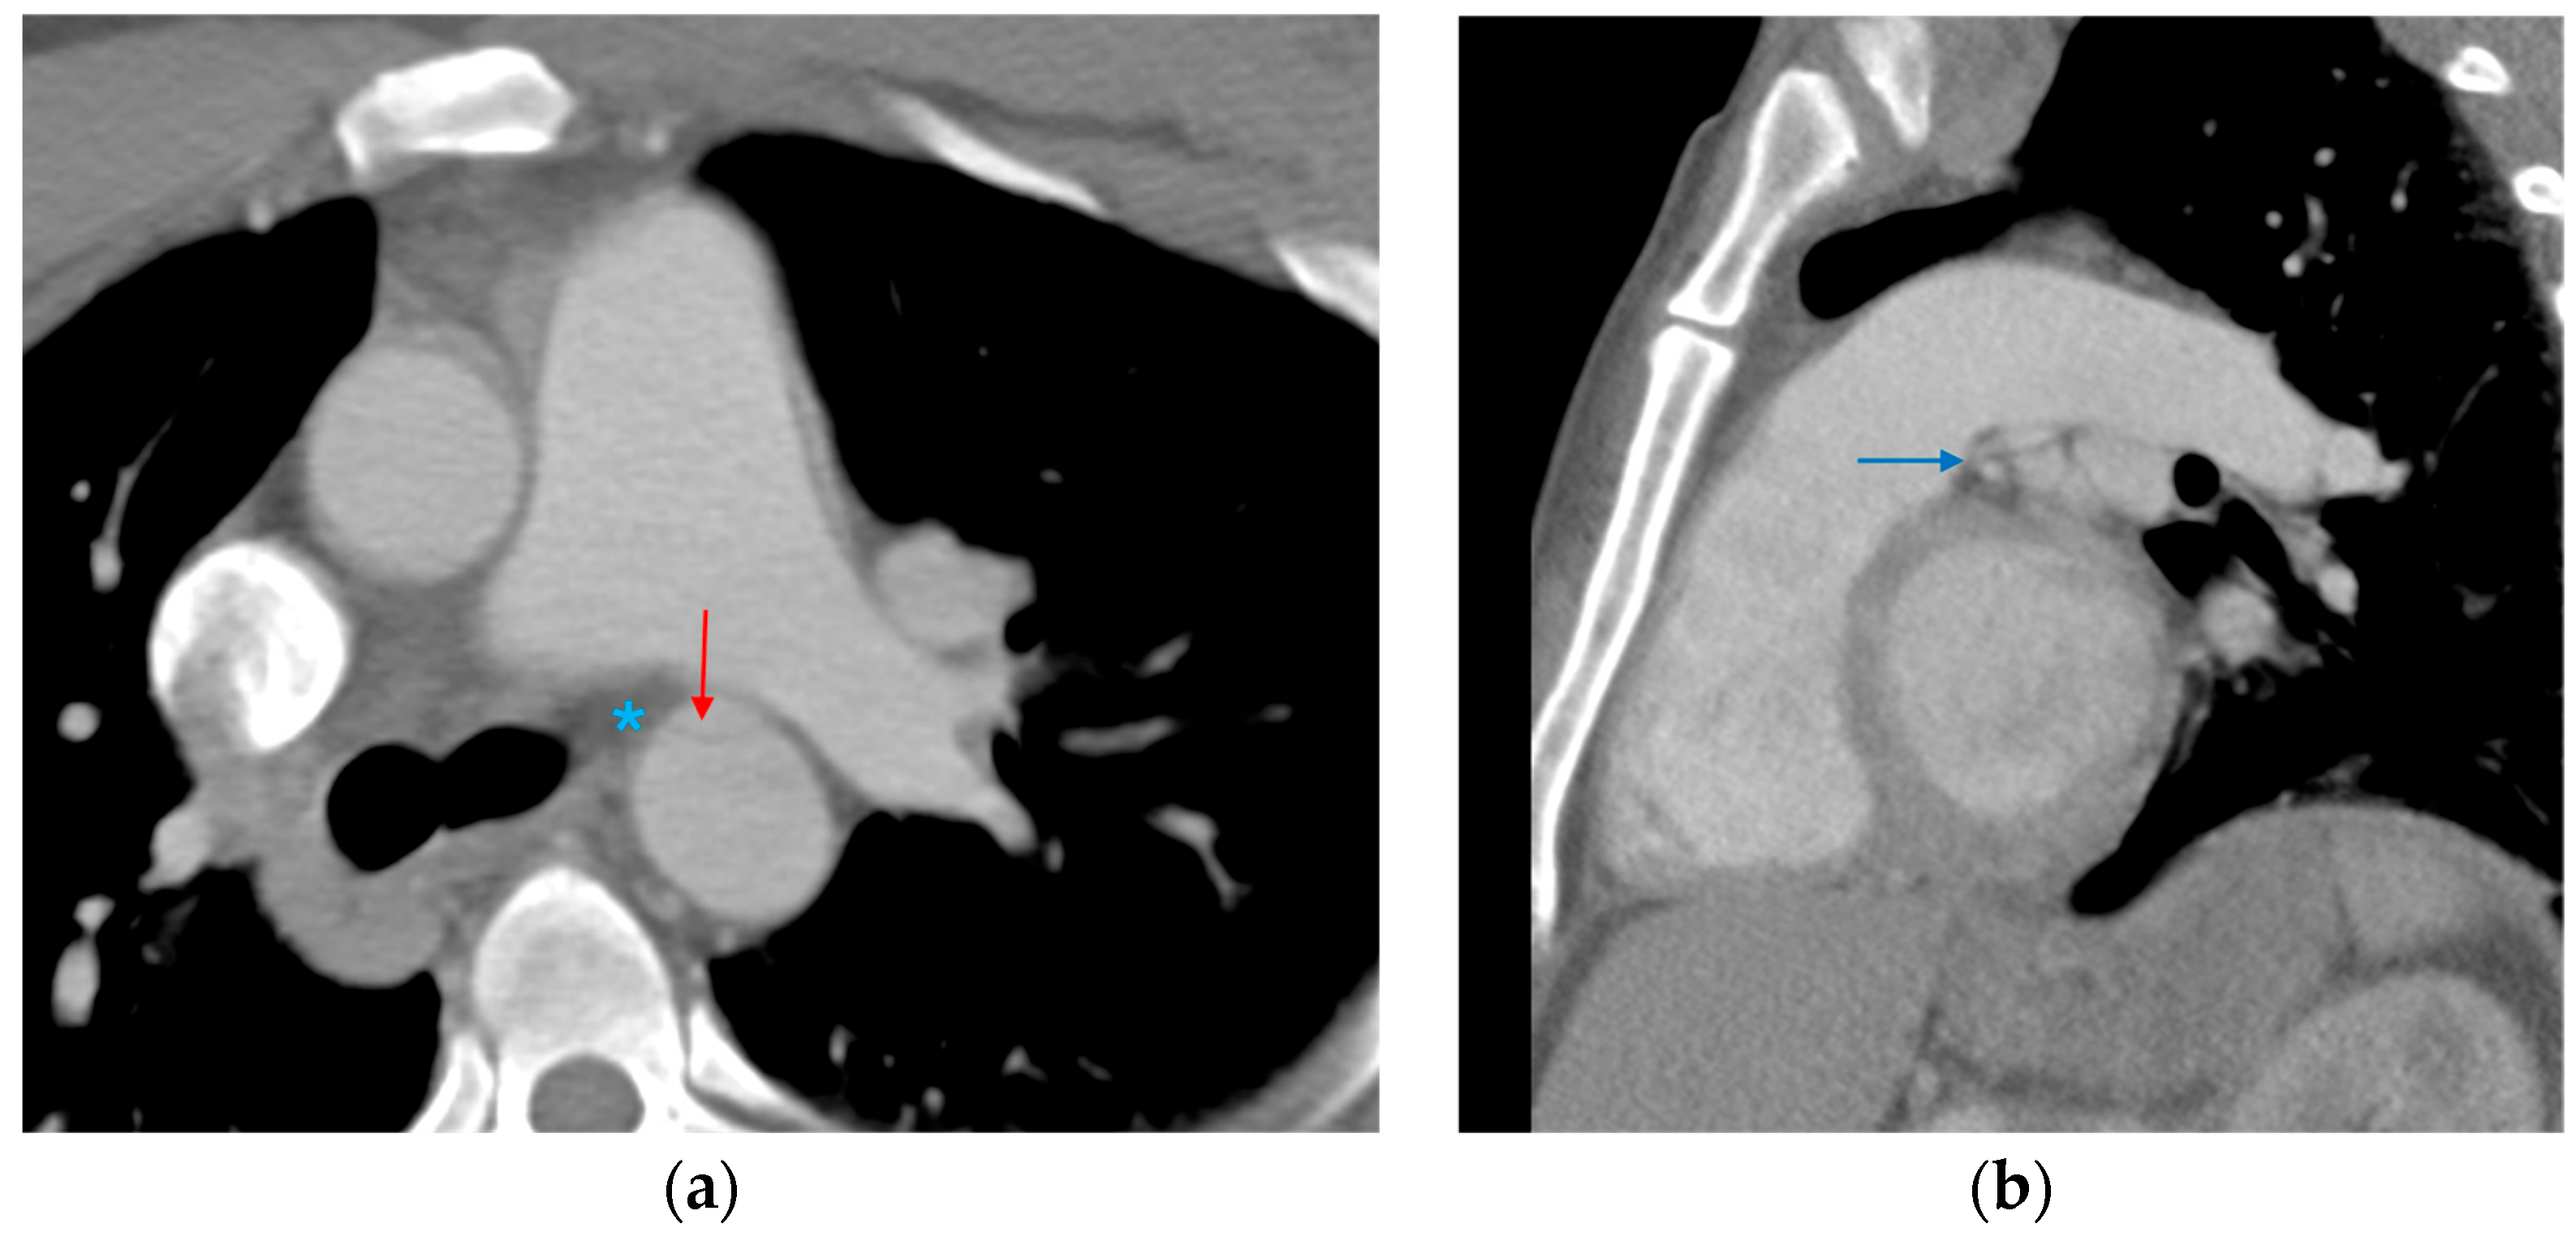

3.1.5. CT Angiography Artifacts

3.1.6. ECG-Gated CT Angiography